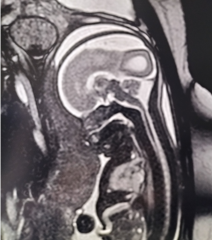

MRI开诊8年以来,完成MRI检查约2.5万多人次,开展了妇科、新生儿、乳腺和其它部位的检查,尤其在全市首先开展了产科MR检查,至今已完成产科检查近4000多例,提高了胎儿和胎盘疾病的检出率,在产前MRI检查技术和诊断方面积累了丰富经验,产科MR成像技术在全市处于领先水平,《磁共振胎儿成像技术的临床应用》被评为天津市卫生系统引进应用新技术填补市空白项目。妇科和乳腺肿瘤MR检查的开展,明显提高了妇科和乳腺肿瘤的诊断、恶性肿瘤的分期、放化疗疗效和预后判断的准确性,极大促进了我院肿瘤学科的临床工作,在妇瘤科、乳腺科MRI检查的数量、技术操作和诊断水平上在全市处于高水平。另外,我科MR特配备儿童专用线圈和防噪音组件,在保障了图像清晰的同时,极大地降低射频和噪音对新生儿的损伤,在新生儿影像诊断方面积累了丰富经验。

胎儿MRI: